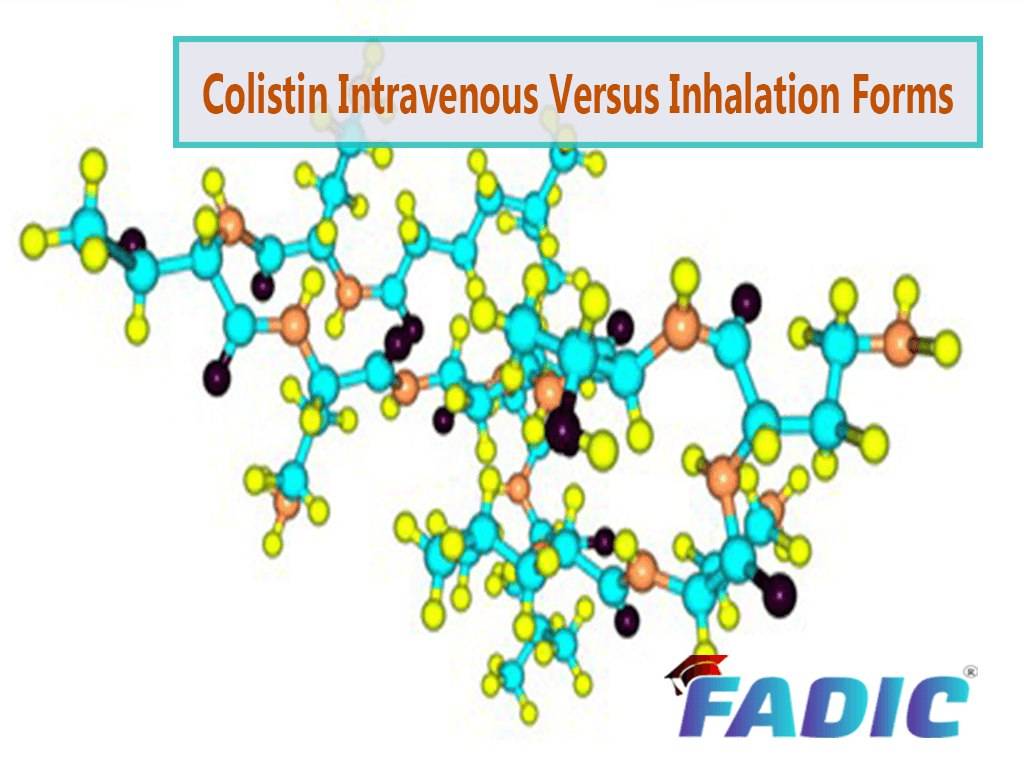

✍️ Important to know more about #Colistin is that it is not used #routinely by inhalation for gram-negative #pneumonia and multidrug-resistant cases (MDRO). ⭕️ Learn More about Colistin #Between Nebulizer and Intravenous Forms: fadic.net/nebulizer-and-…

✍️ Important to know more about #Colistin is that it is not used #routinely by inhalation for gram-negative #pneumonia and multidrug-resistant cases (MDRO). ⭕️ Learn More about Colistin #Between Nebulizer and Intravenous Forms: fadic.net/nebulizer-and-…

fadic.net

Colistin Between Nebulizer and Intravenous Forms

Colistin This article is cornerstone content can be inhaled via nebulizer and has been used in certain settings, including adjunctive therapy to intravenous antibiotics for nosocomial pneumonia,...

✍️ Important to know more about #Colistin is that it is not used #routinely by inhalation for gram-negative #pneumonia and multidrug-resistant cases (MDRO). ⭕️ Learn More about Colistin #Between Nebulizer and Intravenous Forms: fadic.net/nebulizer-and-…

fadic.net

Colistin Between Nebulizer and Intravenous Forms

Colistin This article is cornerstone content can be inhaled via nebulizer and has been used in certain settings, including adjunctive therapy to intravenous antibiotics for nosocomial pneumonia,...

✍️ Important to know more about #Colistin is that it is not used #routinely by inhalation for gram-negative #pneumonia and multidrug-resistant cases (MDRO). ⭕️ Learn More about Colistin #Between Nebulizer and Intravenous Forms: fadic.net/nebulizer-and-…

fadic.net

Colistin Between Nebulizer and Intravenous Forms

Colistin This article is cornerstone content can be inhaled via nebulizer and has been used in certain settings, including adjunctive therapy to intravenous antibiotics for nosocomial pneumonia,...

✍️ Important to know more about #Colistin is that it is not used #routinely by inhalation for gram-negative #pneumonia and multidrug-resistant cases (MDRO). ⭕️ Learn More about Colistin #Between Nebulizer and Intravenous Forms: fadic.net/nebulizer-and-…